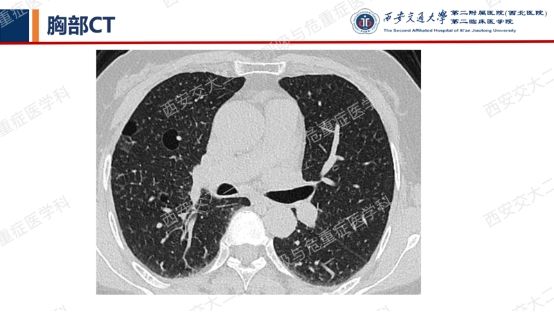

患者呼吸道症状并无太多特异性,还是从影像资料入手,右肺中叶外侧段高密度灶并纵隔及右肺门淋巴结肿大,同时存在双肺多发囊性病变,一元论?多元论?

囊性病变常要鉴别的疾病包括我们第一期的BHDLAM,还有LIP(淋巴细胞性间质性肺炎)、PLCH(肺朗格汉斯组织细胞增多症)、PLCDD(肺轻链沉积病)等。该患者囊性病变特点:沿支气管血管束周围分布,多个囊有血管贴边或穿行于囊肿壁。追问患者有口干不适,进一步行SS-A 52 101.65 AUSS-A 60 47.30AUANA 阳性(+),滴度1:10000 阳性(+),又经唾液流率、泪液流率、唇腺活检及风湿免疫科会诊,诊断干燥综合征。

需要强调的是,LIP影像表现较为复杂——弥漫性GGO+边界模糊之小叶中心性结节+胸膜下结节+支气管血管束增粗+多发囊样气腔各种征象可单独或同时存在。我们最近几期病例会聚焦在弥漫性囊性肺疾病,所以展示的病例影像基本以囊变为主。